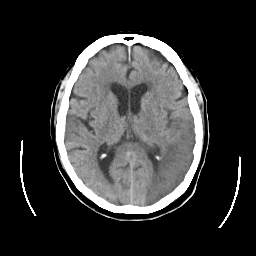

CT Study #2 -- Slice #15